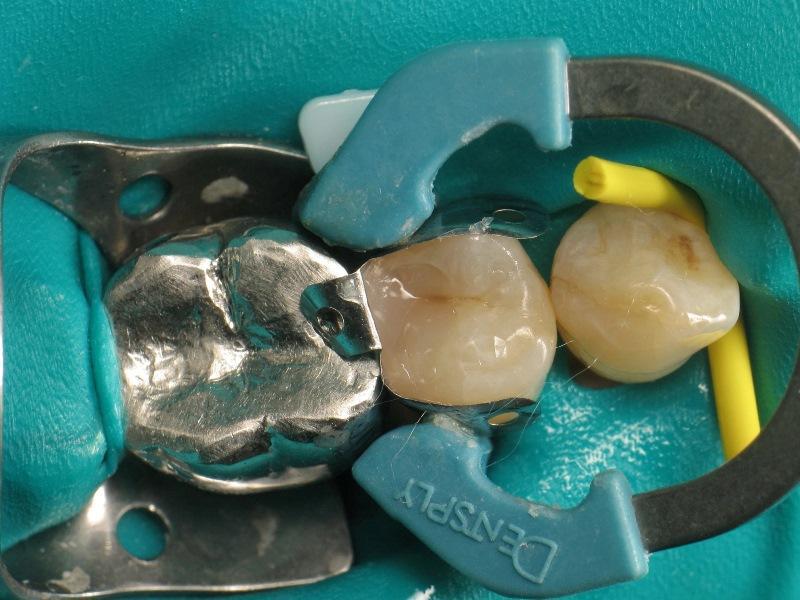

Фото 3: Полость после удаление кариозных тканей.